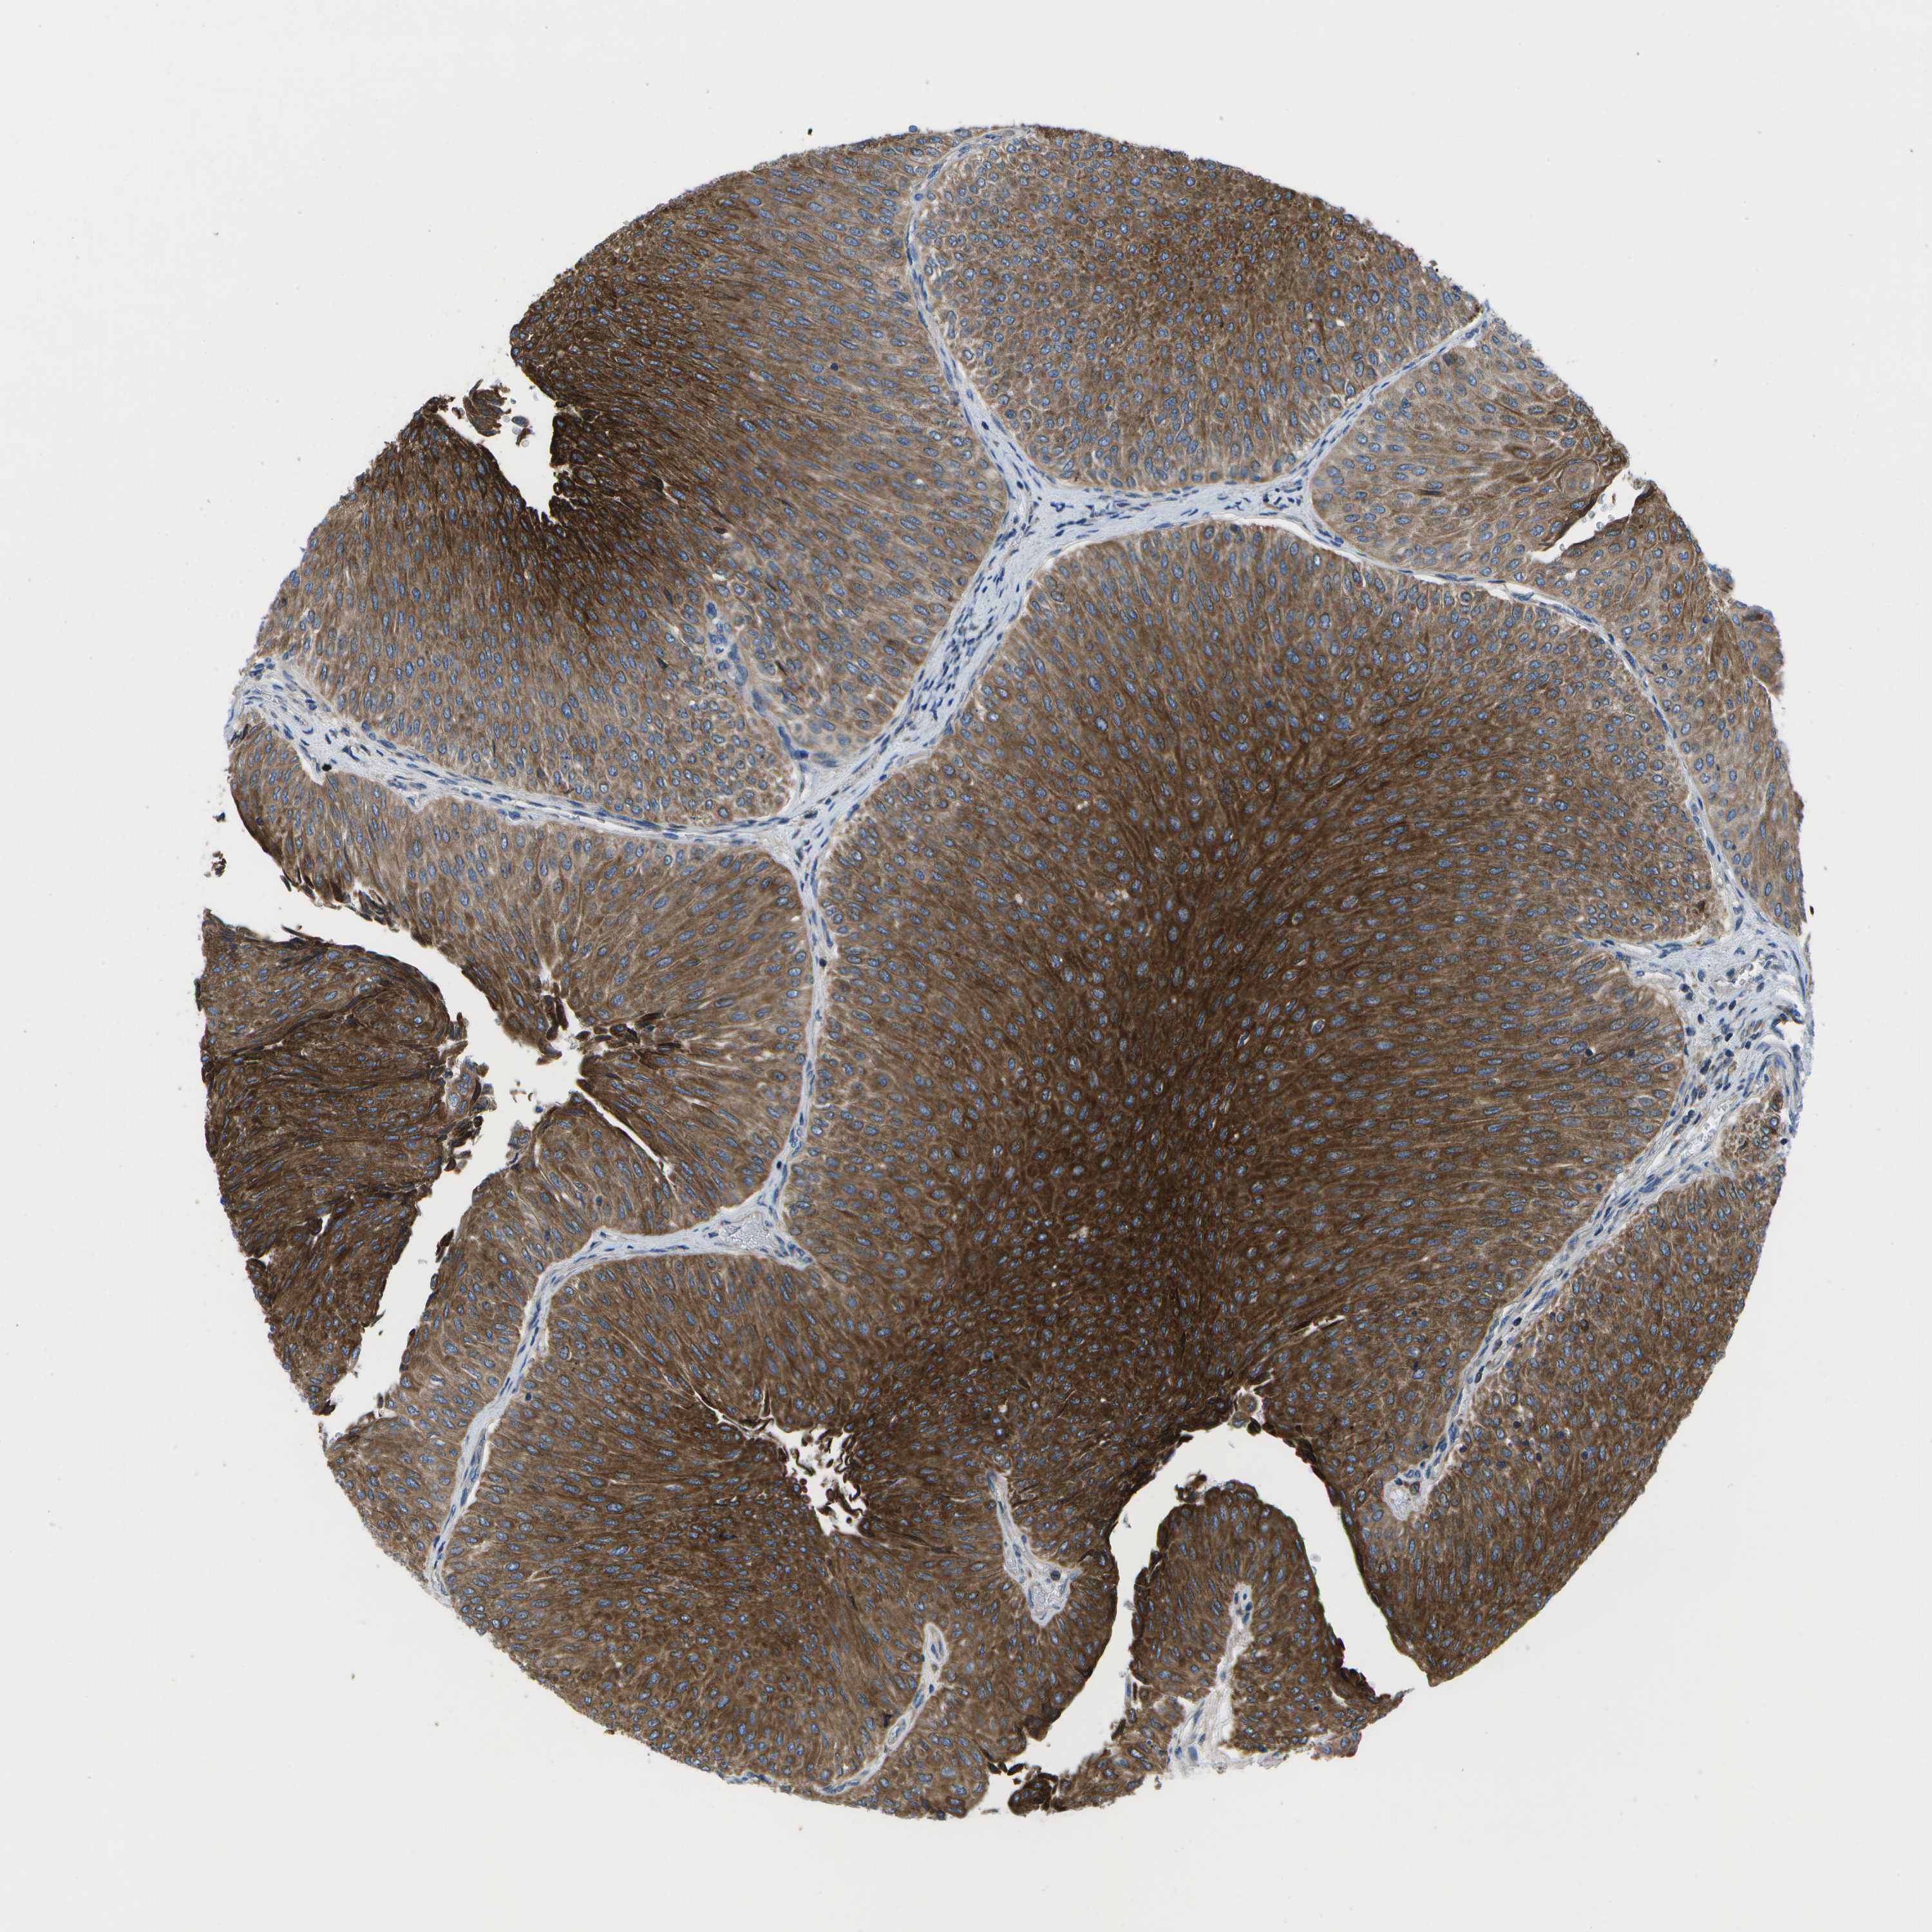

UROTHELIAL CANCER - Protein expressioni

A mouse-over function shows sample information and annotation data. Click on an image to view it in a full screen mode. Samples can be filtered based on level of antibody staining by selecting one or several of the following categories: high, medium, low and not detected. The assay and annotation is described here.

Note that samples used for immunohistochemistry by the Human Protein Atlas do not correspond to samples in the TCGA dataset.

Antibody stainingi

Antibody staining in the annotated cell types in the current human tissue is reported as not detected, low, medium, or high, based on conventional immunohistochemistry profiling in selected tissues. This score is based on the combination of the staining intensity and fraction of stained cells.

Each image is clickable and will lead to virtual microscopy that enables deeper exploration of all samples and also displays staining intensity scores, fraction scores and subcellular localization as well as patient and tissue information for each sample.

Antibody HPA015648

Staining

High

Medium

Low

Not detected

Intensity

Strong

Moderate

Weak

Negative

Quantity

>75%

75%-25%

<25%

None

Location

Nuclear

Cytoplasmic/membranous

Cytoplasmic/membranous,nuclear

Urothelial carcinoma, Low grade

Urothelial carcinoma, High grade